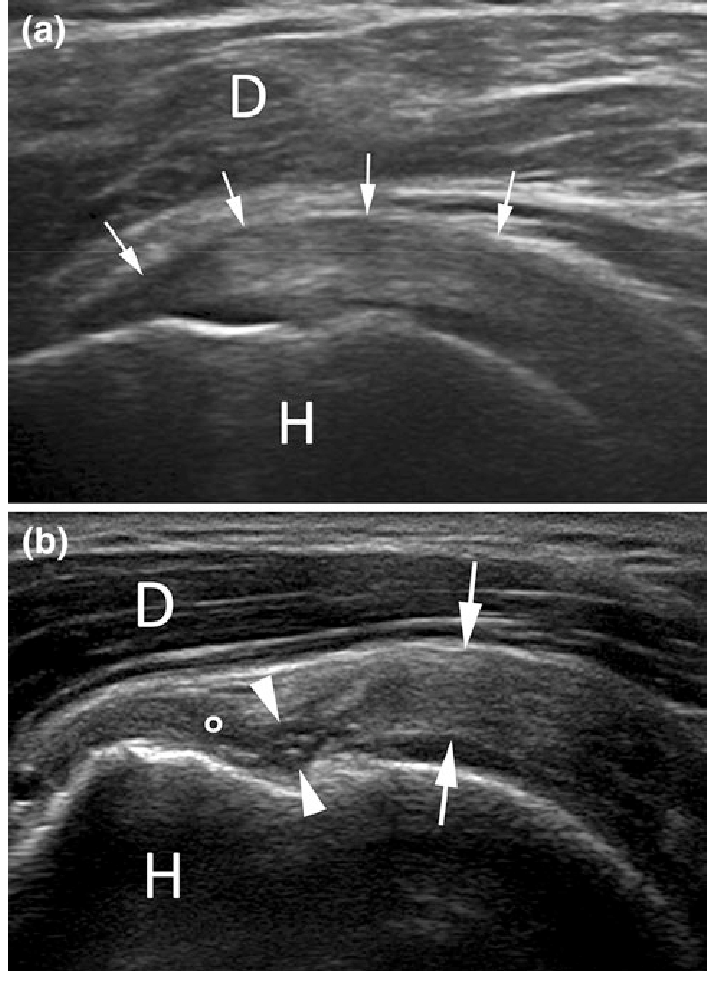

85歲女性患者,主訴左肩疼痛超過6個月,有局部壓痛,無肌肉萎縮現象,圖為左肩部超音波檢查,上圖為旋轉環帶長軸切 面,下圖為短軸切面,最可能之診斷為何?

(B)棘上肌腱斷裂(supraspinatus tendon tear)